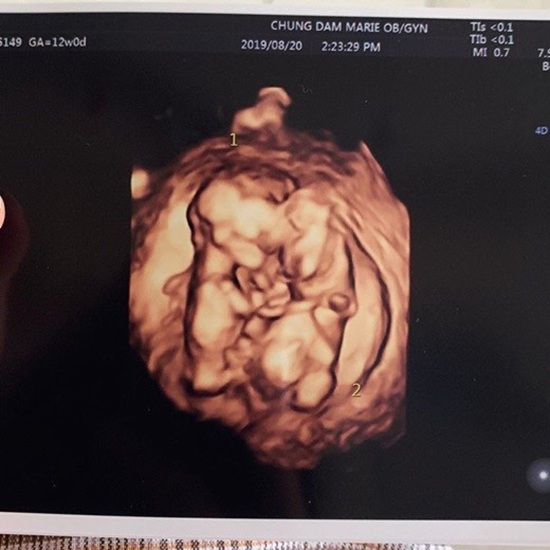

人民網訊 28日,FTIsland樂隊成員崔珉煥的妻子金律喜在個人社交平臺上公布了懷上雙胞胎的消息。金律喜發文稱得知自己懷上雙胞胎后有很多人前來祝福,非常感謝大家。

她接著在文章中說道:“我最近害喜非常厲害,無精打采,但丈夫和婆婆比任何人都辛苦,多虧了他們,我現在在幸福地進行胎教。孩子們就這樣緊緊地貼在一起健康地長大, 再次感謝大家的祝福!

此前,KBS2播出的綜藝節目《做家務的男人們2》中公開了崔珉煥和金律喜夫婦去婦產科的畫面。節目中公開了二人懷的是雙胞胎的消息,當時崔珉煥激動地表示“沒想到竟有這樣的祝福降臨到了我身上","希望雙胞胎能在眾多的祝福中出生"。